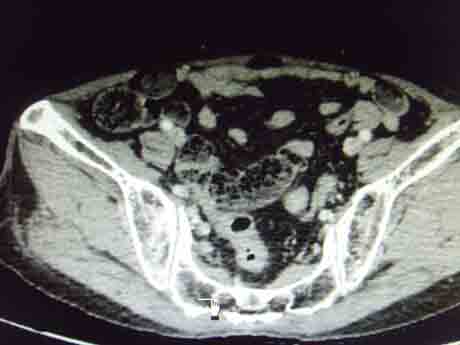

CT51213:盆腔是什么病变?

女,60岁,腹膜后淋巴结肿大。盆腔是什么病变?

右侧附件区可见卵圆形低密度占位,壁厚薄不均,考虑:卵巢囊腺瘤或囊腺癌可能。

卵巢浆液性囊腺癌不除外。

卵巢囊肿吧

卵巢囊腺瘤可能性大